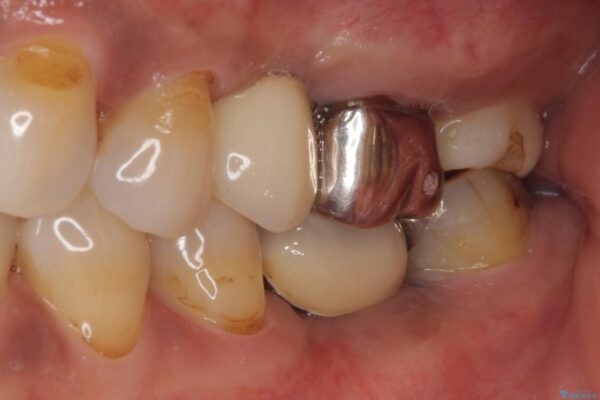

銀歯の装着されている奥歯がしみるとのことで来院された患者様です。

治療計画

銀歯周辺の歯が欠けており、むし歯も進行している状態であったので、オールセラミッククラウンにて補綴治療を行うこととしました。

治療前

• しみる奥歯 オールセラミッククラウンによる補綴治療 治療前画像

治療途中